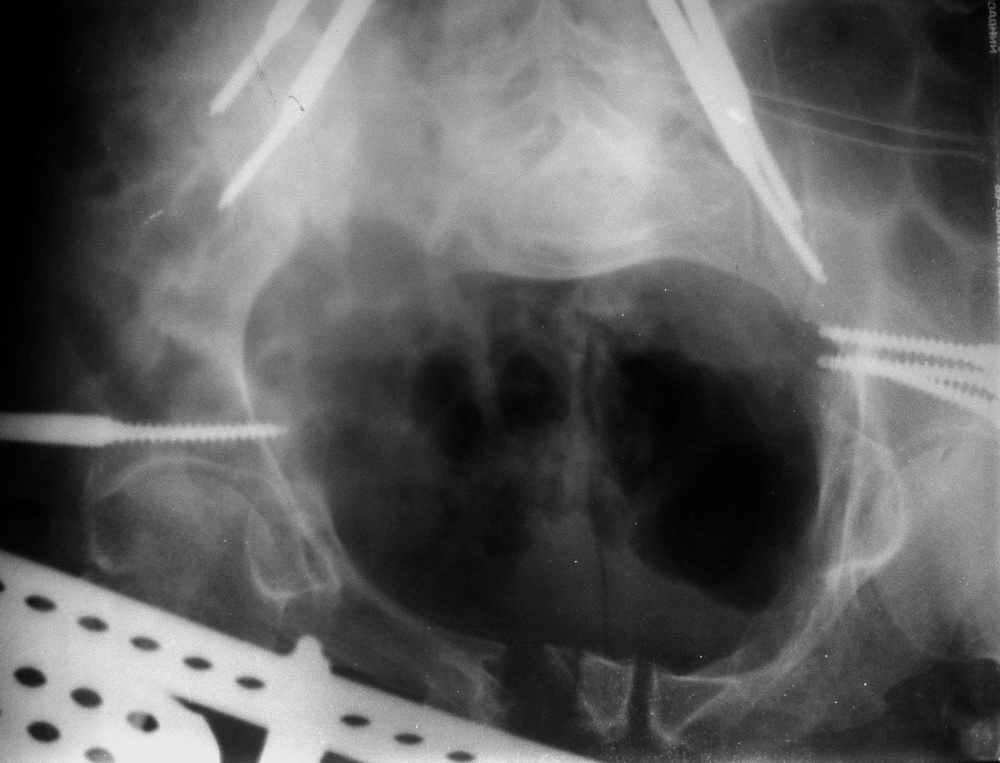

Пример лечения стабильной деформации с вертикальным смещением половины таза.

отеотомия передних и задних отделов, дистракция аппаратом